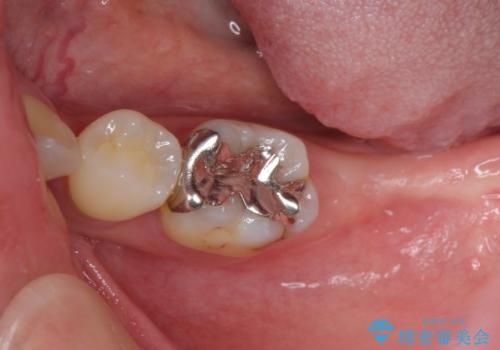

治療期間を短縮することが可能となった、ストローマン社のSLActiveというインプラントを使用し、抜歯からクラウンが装着されるまで6ヶ月という短期間で終えることができました。

咬み心地はもちろん、清掃性もご自分の歯とほとんど変わらない状態となり、患者様には大変満足していただきました。